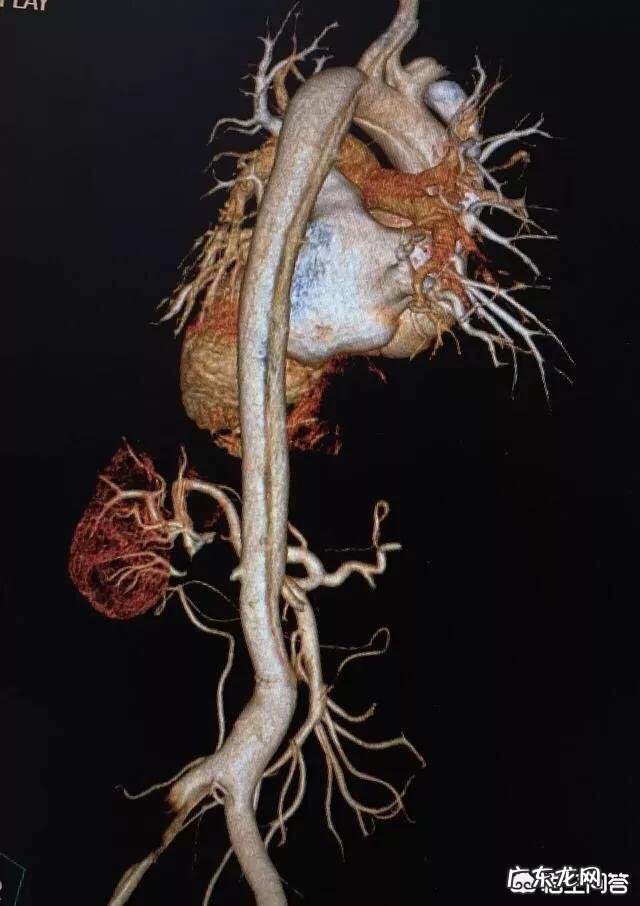

需要特别提一下的就是出现后背部疼痛的心血管疾病,比如心肌梗死,动脉夹层等 。这类疾病是跟死神抢时间,时间就是生命,要快速就医,快速诊断和治疗 。耽误一分钟都有可能抢救不回来 。

文章插图

这是一个32岁的男性,一名快递员,因为前一天搬运重物,出现了后背疼,因为是扭伤,没有重视,晚上是疼痛加剧,伴发大汗淋漓就诊 。医生一听心脏,不对,马上建议做了检查,考虑主动脉夹层(供应人体的大血管撕裂了)并且是最危险的,撕裂到了心包,心包积血,随时会出现生命危险 。